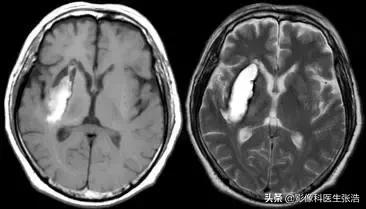

(4)慢性期:为2周以上。

含铁血黄素和铁蛋白形成并进一步氧化为氧化铁,同时由于巨噬细胞的吞噬作用使含铁血黄素沉着于血肿周边部,其使T2弛豫时间缩短,因此在血肿的周边部出现低信号的影像环带,其余仍为高强度信号表现。

脑出血慢性期

所以血肿中心T1加权为等信号,T2加权为高信号。血肿周边T1加权像为稍低信号,T2加权像为低信号。